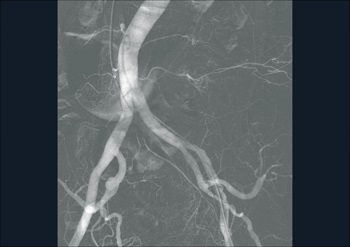

— Субстракционная ангиография

Ziehm Vision RFD - уникальный мобильный рентгеновский аппарат с возможностью многостороннего клинического применения. Плоскопанельный детектор аппарата дает отличные высокоточные изображения, обеспечивая прекрасную визуализацию для инвазивной радиологии, нейрохирургии, сосудистой хирургии, кардиологии и при инвазивных процедурах, таких как аневризма абдоминальной аорты или ЧТКА, и находит также применение в гибридных областях,

как например, при имплантации аортального сердечного клапана.

Компания Ziehm Imaging впервые предоставила возможность использовать все достоинства плоскопанельных детекторов в мобильных установках. Благодаря плоскому детектору 30 х 30 см область видимого поля увеличилась в 2.5 раза по сравнению с обычным усилителем изображения 23 см. Отсутствие S-образной дисторсии, широкий динамический диапазон и превосходное отображение всех анатомических деталей делает этот аппарат идеальным выбором для широкого спектра клинических процедур.

Ziehm Vision RFD - уникальный мобильный рентген с плокопанельным детектором для многостороннего клинического применения. Аппарат дает отличные высокоточные результаты в инвазивной радиологии, нейрохирургии, сосудистой хирургии, кардиологии и при инвазивных процедурах, таких как аневризма абдоминальной аорты или ЧТКА, и находит также применение в гибридных областях, как например, при имплантации аортального сердечного клапана. Специальный программный пакет SmartVascular позволяет выполнять цифровую субтракционную ангиографию, в том числе с возможностью использования CO2 как контрастного вещества. Возможность установки дополнительных потолочных мониторов и внешнего интерфейса управления, а так же расширенное орбитальное вращение штатива делают Ziehm Vision RFD незаменимым аппаратом для многофункциональных операционных.

• Программный пакет для сосудистой хирургии: DSA, MSA, RSA и CО2